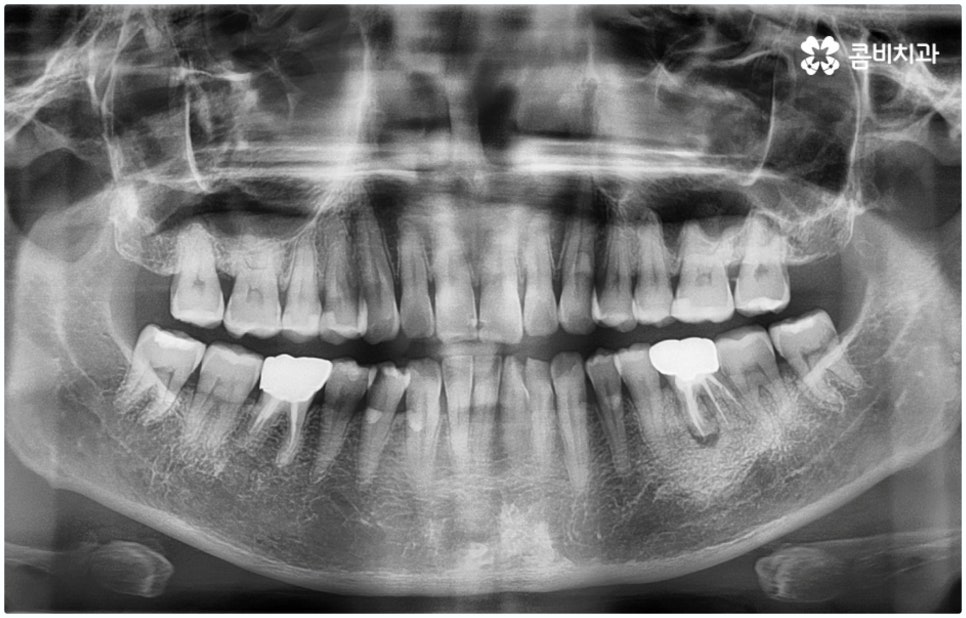

예를 들어 충치가 악화되어 세균이 치아 내부 치수 조직까지 침투한 경우 감염된 신경을 깨끗하게 제거하고 신경관 내부를 생체친화 충전재로 밀봉한 후 크라운으로 덮어 씌워주는 신경치료를 하게 되는데, 이때 감염 부위가 제대로 제거되지 않거나 2차 감염이 일어나 손상이 치아 뿌리까지 진행되면 자연 치아를 살리는 게 어려워 질 수 있습니다. 시기를 놓치면 재신경치료, 치근단 절제술 등의 보존 치료 역시 소용이 없어질 수 있으니 만약 신경 치료를 받은 치아가 있다면 더욱 신경써서 위생 관리에 주의하시고 검진을 통한 관리를 게을리 하지 않으시길 권유드리고 있어요.

그렇기 때문에 무조건 보다 빠르고 간편하다고 해서 원데이임플란트 방법을 고집하기 보다는 개인 상태에 따라 필요한 과정을 세심하게 맞춤 진행할 수 있도록 경험이 풍부하고 노하우가 뛰어난 의료진에게 치료 받는 것이 중요한 거예요. 즉 3D CT 등 정밀 검진 장비를 이용하여 환자분들의 치아 및 잇몸 상태, 치아 배열과 교합상태, 주변 치아와의 관계 및 조화까지 꼼꼼하게 파악할 뿐 아니라 턱뼈, 혈관, 신경 등 구강 전체를 함께 분석한 후 체계적인 시술 계획을 세워 각자에 맞는 방법으로 무리하지 않게 수술을 진행할 수 있는 숙련된 의료진과 함께 하는 것이 무엇보다 중요하다고 할 수 있습니다.